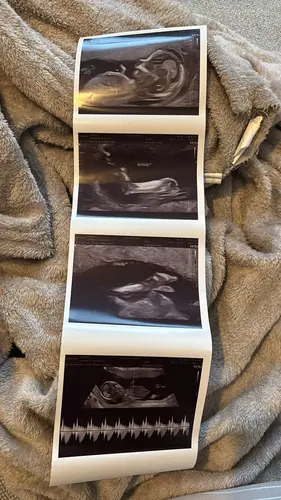

En wat denken jullie op basis van deze echo? 😀

Ik denk een jongetje